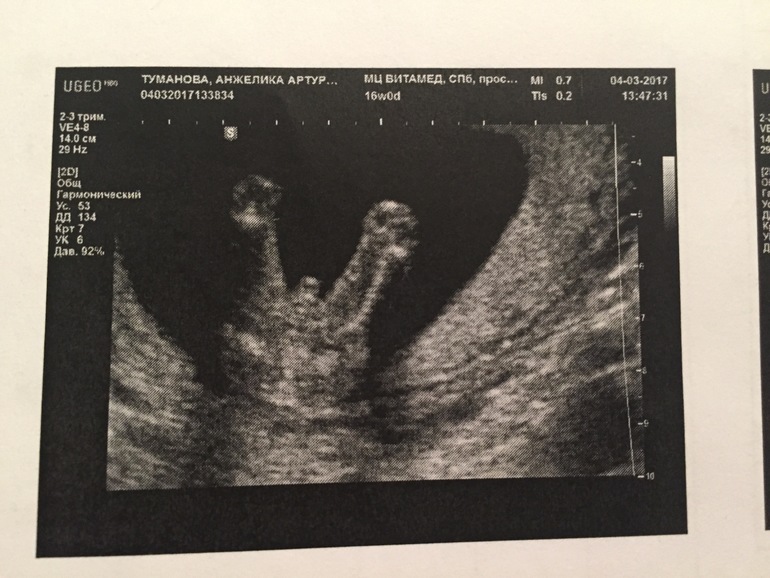

УЗИ на определение пола)

Беременность - 3На днях, 4 марта ходили с мужем на УЗИ.

У нас будет второй сын!!!

По результатам:

на 4 марта было 16 недель и 1 день.

Вес плода 145 грамм.

КТР - копчико-теменной размер плода 11,05 см.

БПР - бипариентальный размер (размер головы между висками) 3,26 см.

ДБК - длина бедренной кости 2,03 см.

ОЖ - объем живота 10,17 см.

ЛЗР - лобно-затылочный размер 4,15 см.

ОГ - объем грудной клетки 12 см.

Чистота сердечных сокращений 149 ударов в минуту

Плацента расположена по задней стенке, 0 степень зрелости. Нижний край плаценты высоко над уровнем внутреннего зева.

Шейка матки не укорочена, цервикальный канал 4 см, внутренний зев закрыт.

Околоплодных вод нормальное количество.

Пуповина имеет 3 сосуда, обвития пуповины вокруг шеи нет.